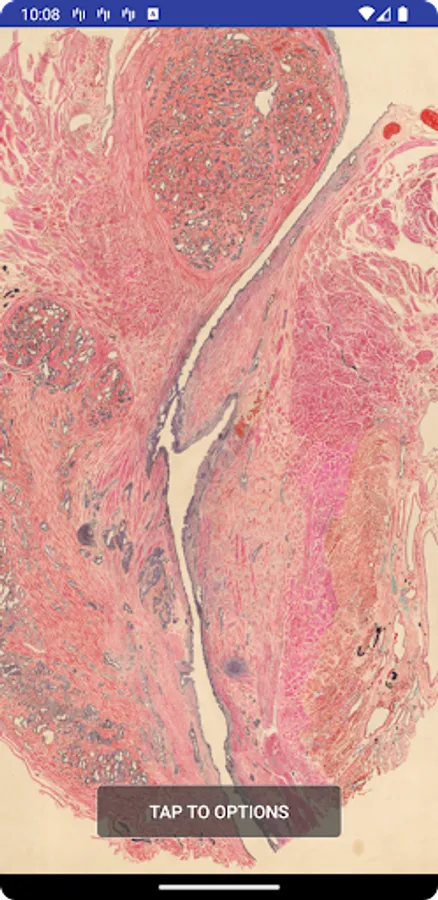

The wallpaper of the Salvador Gil Vernet Collection of Urology Drawings contains a selection of drawings from the Salvador Gil Vernet Collection of Urology Drawings. This collection is composed of more tan 580 urology drawings illustrating gross anatomy of the male pelvis and perineum, urogenital pathology and surgical techniques in urology.

The collection includes watercolor, charcoal, pencil and ink drawings completed between 1940 and 1970, which have been restored and catalogued in the last two years. Some are originals published in his books Urogenital Pathology (1944-1955) and Morphology and Function of the Vesico-Prostato-Urethral Musculature (1968); others were presented at national and international conferences and in other scientific literature.